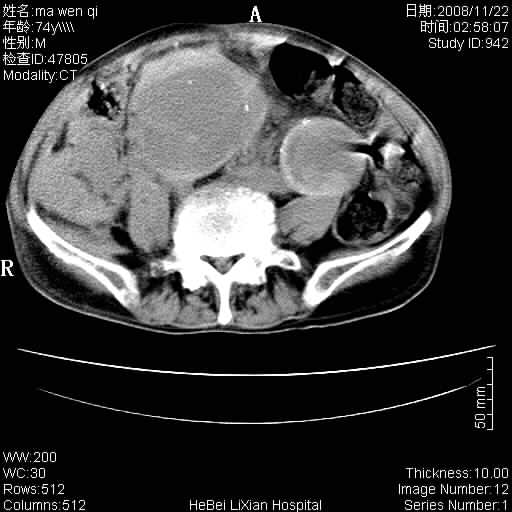

患者男 74岁.突然昏迷,休克6小时.血压70/30,头颅ct未见异常,既往体健.

补充病史,保留导尿10小时,尿袋内只有少许尿液,患者于住院后15小时后去世.

腹主动脉、双侧髂动脉夹层动脉瘤破裂出血进入腹腔。

1)考虑双侧髂动脉瘤并右侧动脉瘤破裂出血,右侧腹膜后及腹腔积血。2)双侧腹股沟疝。

1)考虑,腹主动脉、双侧髂动脉夹层动脉瘤破裂伴右侧腹膜后及腹腔积血。2)双侧腹股沟疝。